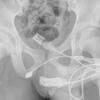

O venezuelano chegou ao hospital com fortes dores e imagens de raio-x mostraram a garrafa alojada dentro do corpo. Ele foi transferido para outro hospital, onde passou por uma cirurgia.